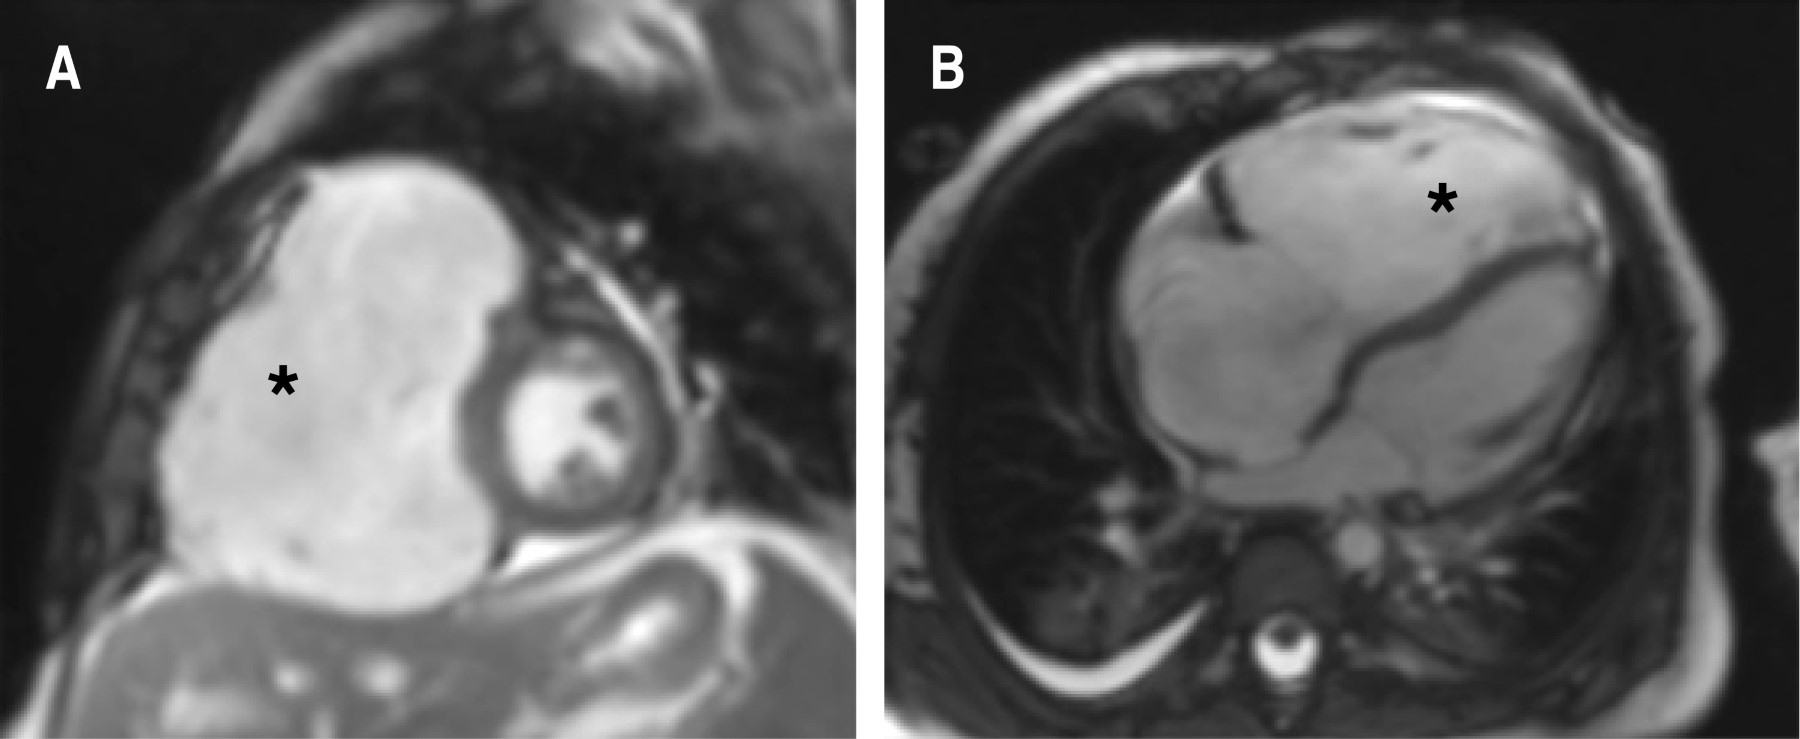

Se decidió complementar con estudio de resonancia magnética cardiaca, la cual reportó dilatación de la vena cava inferior, aurícula derecha de 38 × 36 mm con área de 13.4 cm2, ventrículo derecho con diámetro diastólico de 42 mm (z-Score: + 4.83), anillo tricuspídeo de 24 mm con insuficiencia grave y el tabique interauricular con abombamiento hacia la izquierda sin evidencia de cortocircuito, disfunción sistólica grave del ventrículo derecho con una fracción de eyección de 21% con sospecha diagnóstica de anomalía de Uhl (Figura 3).

Concomitantemente, la resonancia magnética cardiaca en los últimos años se ha convertido en una herramienta útil en el abordaje diagnóstico de las cardiopatías congénitas, por lo que en esta entidad desempeña un papel importante. La resonancia magnética reporta paredes del ventrículo derecho delgadas con ausencia de miocardio en la pared libre y pocas trabeculaciones apicales, sin infiltración grasa, con disfunción sistólica y aumento del volumen diastólico final.2,5

En estos estudios se evidencia la contractilidad disminuida del ventrículo derecho, pero es importante recalcar que la función del ventrículo izquierdo está preservada.2

Figura 3